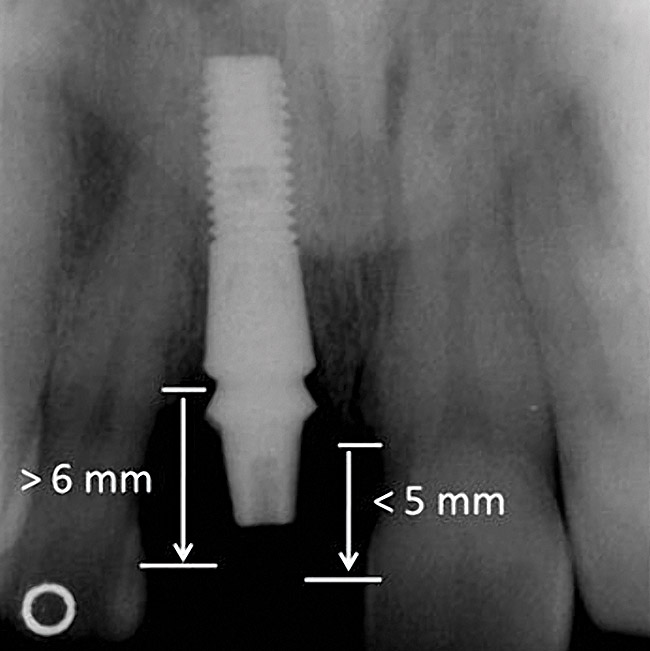

Figure 2  Identification of sufficient inter-radicular space: The radiographic representation of inter-radicular space (Fig 2) reveals abundant space for a single-tooth implant; at the alveolar crest, > 6 mm of interproximal space is available for placement of a 4-mm implant without encroaching on bone and periodontal ligament at the adjacent teeth. The 5-year-follow-up radiograph (Fig 3) reveals the interproximal maintenance of bone at this implant/abutment interface and adjacent teeth, in part due to proper planning and implant placement.

Figure 2

Figure 3  Identification of sufficient inter-radicular space: The radiographic representation of inter-radicular space (Fig 2) reveals abundant space for a single-tooth implant; at the alveolar crest, > 6 mm of interproximal space is available for placement of a 4-mm implant without encroaching on bone and periodontal ligament at the adjacent teeth. The 5-year-follow-up radiograph (Fig 3) reveals the interproximal maintenance of bone at this implant/abutment interface and adjacent teeth, in part due to proper planning and implant placement.

Figure 3